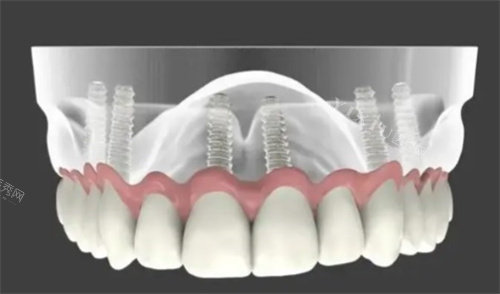

种植牙:国产种植牙1880元/颗起,韩国登腾种植牙3800元/颗起,瑞士ITI种植牙8800元/颗起;

全口修复:半口种植牙30000元起,全口种植牙60000元起;